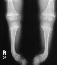

X-RAY STUDIES:

- "cupping" of the distal radius and distal femur

- widening of the physis

- angular deformities

10 months later on follow-up she had a noticeable decrease in her tibial

bowing along with almost complete resolution of the growth plate abnormalities.